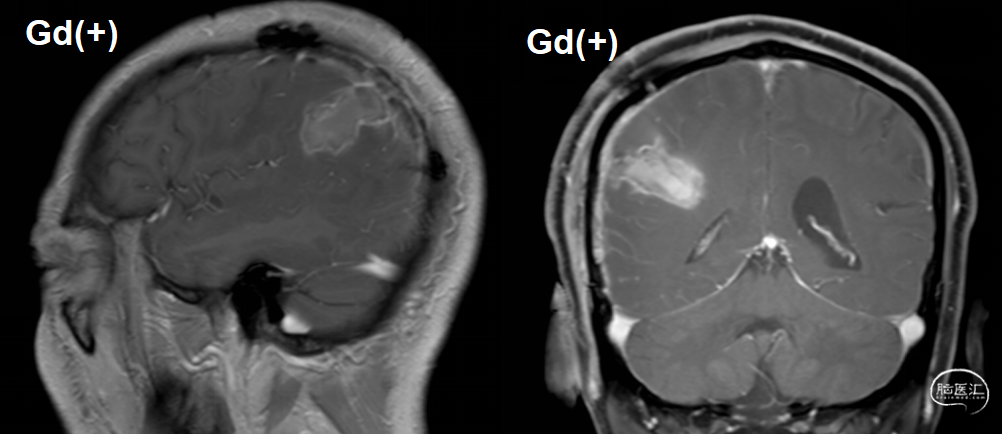

术前MRI显示右额顶病灶,约4.1*3.5*2.9cm,T2等高混杂信号,T1等低混杂信号,明显不均一增强,ADC呈低信号。

术前诊断考虑右额顶高级别胶质瘤或转移瘤。